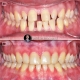

درمان ارتودنسی بدون جراحی و بدون کشیدن دندان در کیس دیپ بایت همراه با کنت اکلوزال و باکال کریدور های وسیع در مدت ۲۰ ماه انجام شد.

Non surgical and non extraction orthodontic treatment of deepbite case with occlusal cant and large buccal corridors done within 20 months.